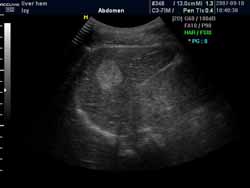

超聲引導下的局部治療也就是在彩超的實時引導下,通過經皮肝穿刺將硬化劑、抗血管生成的藥物直接注入瘤體內部,能使血管瘤組織脫水固定,組織細胞蛋白質凝固變性,局部血管血竇內皮壞死,血栓形成,導致細胞死亡和纖維化,從而達到治療目的。治療方法簡單,不需要特殊設備,痛苦小,療效明確。

(血管瘤超聲表現可見高回聲血管團影)

(超聲穿刺針直接對瘤體進行注射治療)